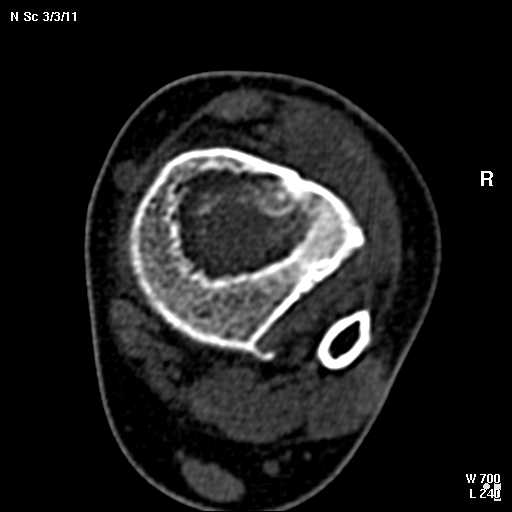

В обсуждении темы возникла необходимость дополнительных данных.

КТ изображения передаю на мой взгляд самые демонстративные. Их любезно записал коллега,

проводивший исследование в другом городе.